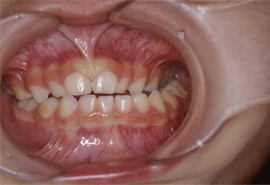

(3)片側性交叉咬合:上下の奥歯が横にずれて中心があわない。

![]() |

【写真3】 昼間も継続する指しゃぶりにより交叉咬合を生じた3歳児。 |